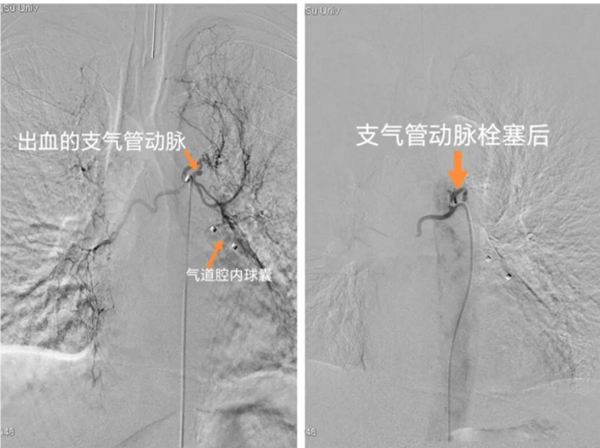

接着,介入放射科团队无缝衔接。在介入放射手术室,张建主任带领韩壮等团队成员,在基础麻醉下行“支气管动脉造影栓塞术”。术中,医生通过大腿根部一个针眼大小的穿刺点,将导管精准地送到了肺部出血的血管区域。造影显示,患者双侧支气管动脉增粗,其分支增多、增粗,扭曲、紊乱,左侧支气动脉内镜下球囊封堵术后改变,似见少量造影剂外溢。团队凭借娴熟的技术,通过微导管注入栓塞剂,精准地封堵了这根“惹祸”的血管,造影复查显示出血点已被精准封堵。